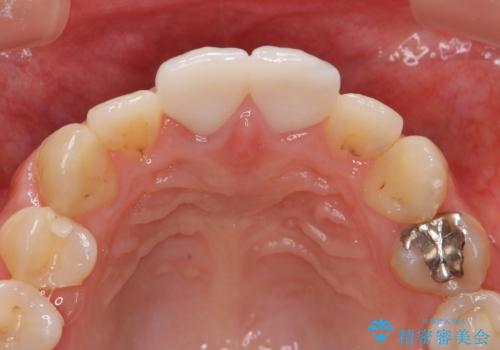

虫歯の徹底的な除去、根管治療を行いセラミック治療に入る前の環境をしっかりと整えたのち審美的なジルコニアセラミックで治療を仕上げました。

- 26.4万円(仮歯×2・ファイバーコア・ジルコニアクラウン×2)費用は治療当時の料金となります